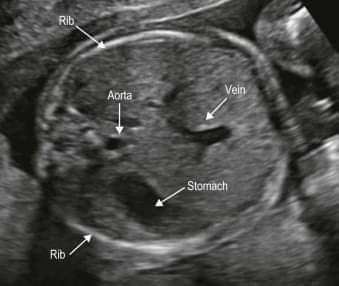

Ellipse

AC :

measurements